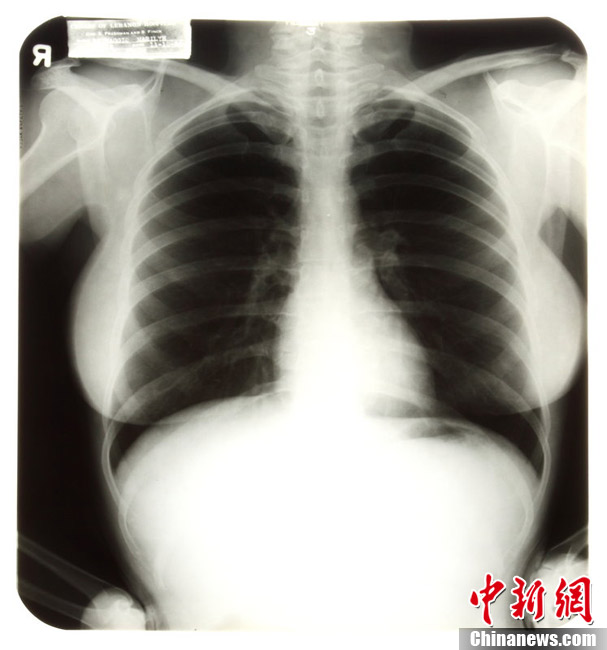

拍卖梦露的X光片:当地时间2010年4月14日,美国,将拍卖的玛丽莲-梦露生前遗物。图为梦露的X光片。图片来源:东方IC 版权作品 请勿转载